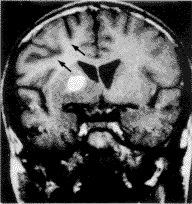

四、瘤旁水肿与肿瘤扩散:位于基底节的9例中,8例见肿瘤旁有轻微水肿带,1例无瘤旁水肿;2例位于丘脑者未见明显瘤旁水肿。9例位于基底节的肿瘤中,4例见肿瘤向对侧基底节扩散(图6)。位于丘脑的2例中,无一例向对侧扩散。

五、占位征象与同侧皮层萎缩: 基底节及丘脑生殖细胞瘤占位征象多不明显,其中5例基底节生殖细胞瘤可见同侧大脑皮层萎缩征象,表现为外侧裂及脑沟增宽(图7)。

图6 右侧基底节生殖细胞瘤。增强扫描见 图7 同侧大脑皮层萎缩(箭头与

肿瘤向对侧扩散(箭头) 图3~5为同一病人)

基底节及丘脑生殖细胞瘤扩散形式与松果体区生殖细胞瘤的室管膜直接蔓延或沿脑脊液种植扩散有所不同,肿瘤可沿纤维束向对侧基底节扩散。本组11例中4例见肿瘤向对侧扩散,表现为斑点样增强影。此外,基底节及丘脑生殖细胞瘤可伴有同侧大脑皮层萎缩。早期多数作者认为此征象是基底节及丘脑生殖细胞瘤的特征性表现,后又有作者认为基底节及丘脑任何肿瘤均可有此改变。Kim[5]和Higano等[6]发现,当基底节及丘脑生殖细胞瘤形态不规整并侵及内囊时多伴有同侧大脑皮层萎缩,因此提示,半球萎缩为内囊受累所致。本组有5例伴同侧额叶盖部萎缩。